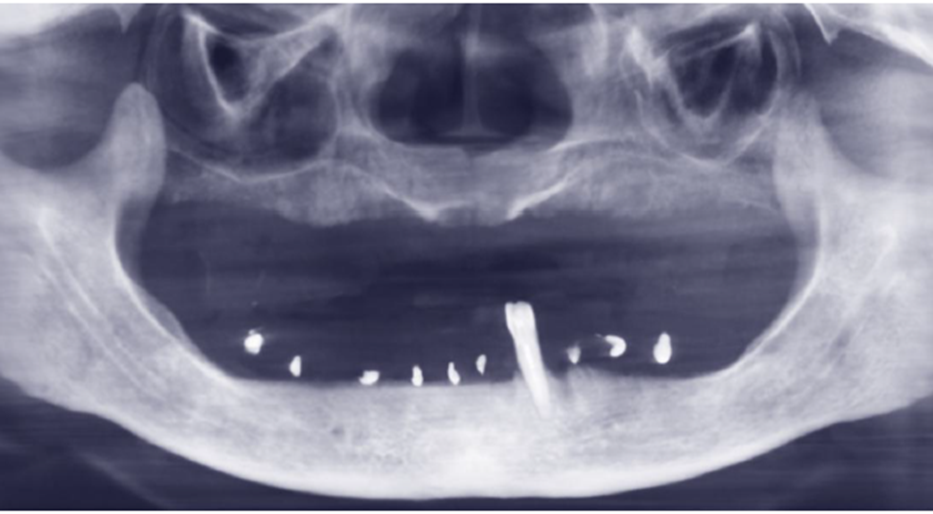

Figura 3 – Raio-X panorâmico inicial sem próteses removíveis em boca.

Paciente do sexo feminino, 61 anos, compareceu ao consultório apresentando ausência de todos os dentes da arcada inferior, com exceção do dente 33. Apesar da condição edêntula parcial, apresentava boa quantidade e qualidade de tecido ósseo remanescente. Utilizava uma prótese parcial removível e relatava como principais queixas a dificuldade mastigatória e a insegurança causada pela ausência de dentes fixos.